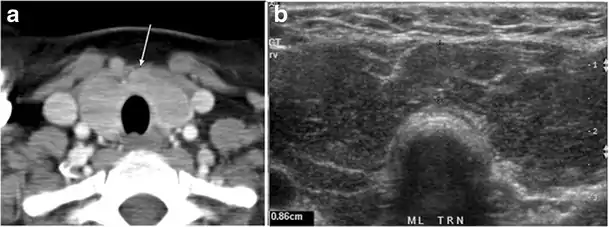

Fig. 4. A 45-year-old male patient presented with anterior mediastinal metastatic PTC lesions and occult primary on imaging. Histopathology examination of the resected thyroid gland revealed micro-foci of PTC; the largest, in the isthmus, measured 4 mm. a transverse greyscale ultrasound of the thyroid demonstrates homogeneous gland with normal echogenicity and size. No focal lesion or micro-calcifications. b Non-enhanced CT scan obtained as part of PET/CT examination shows a heterogeneous, large, relatively dense anterior mediastinal mass (white arrow) with peripheral calcification (arrowheads). Thyroid gland has normal CT appearance with no abnormal FDG uptake (not shown).[1]

Fig. 14. A 19-year-old male patient known to have multi-nodular goiter and FNA, showing underlying Hashimoto's thyroiditis. a, b Sagittal and transverse greyscale and colour Doppler ultrasound of the neck demonstrate a hypoechoic enlarged right thyroid lobe with small hyperechoic regenerative nodules and marked hypervascularity (white arrows). c, d Enhanced axial CT scan images of the neck demonstrate a heterogeneously enhancing and enlarged thyroid gland, left more than right lobe, and the trachea is markedly narrowed.[1]